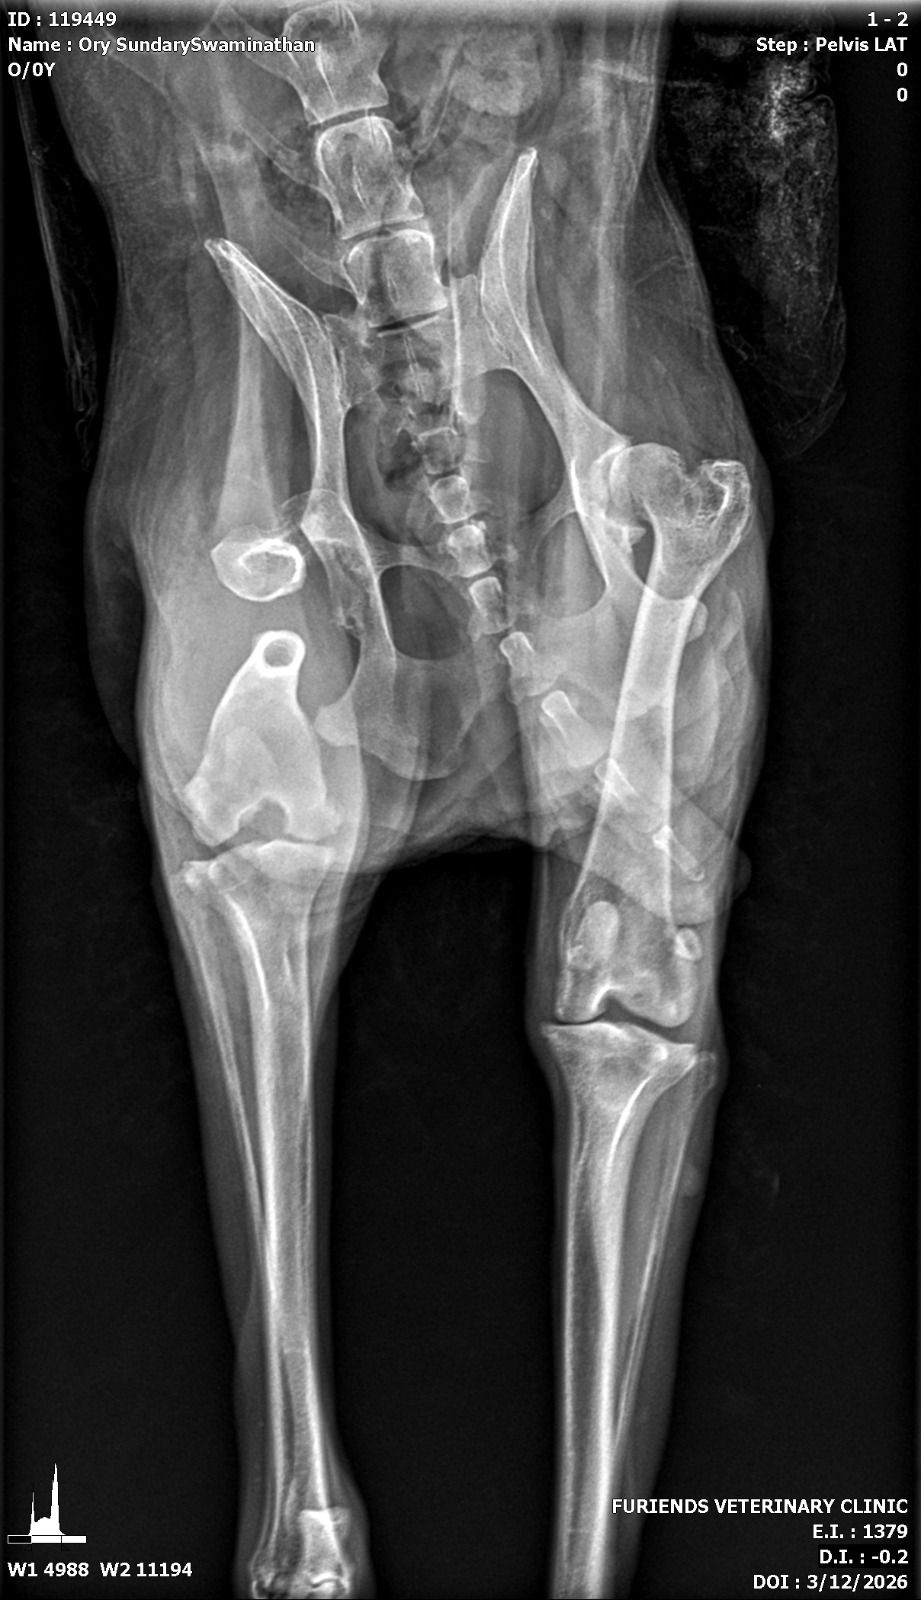

I returned to Singapore after a long trip, spending the 13-hour flight mentally preparing myself for the next phase of my life—career growth, personal goals, and how I was going to move forward. More than anything, I couldn’t wait to pick up Ory from the boarding home I had left him at. I knew he wasn’t walking, but I assumed it was just his usual leg cramp. Little did I know, a huge shock was waiting for me. The moment I saw him, my heart sank—his leg looked broken, and deep down I knew something was very wrong. The Ory who loved to walk was struggling to even take a step, yet he kept trying. I held onto hope that it was just a muscle or ligament issue, but the next day, I rushed him to the nearest vet where an X-ray confirmed my worst fear: a broken femur.

Ory xray Ory xray1

I was given two options—amputation or putting him down. My world was shaken. The vet explained that due to his age, arthritis, and weak remaining legs, there was no guarantee he would be able to walk again after amputation. It all came down to his quality of life. I was referred to a specialist, and thankfully, I managed to get an appointment that very same day. The specialist echoed the same options but gave me a glimmer of hope—despite his injury, Ory was still trying to move, still fighting. He was placed on a fentanyl patch to manage the pain, but that night, he reacted badly, becoming extremely vocal and uncomfortable.